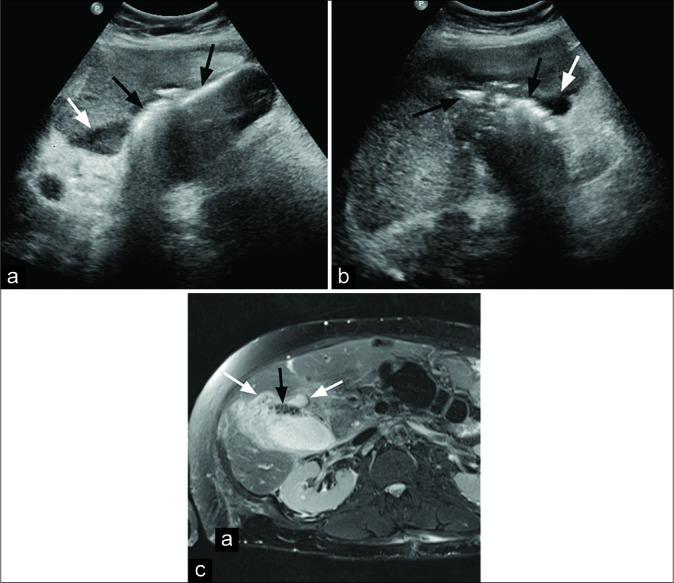

经皮胆囊造瘘术治疗气肿性胆囊炎的安全性和有效性

The objective of the study was to evaluate the safety and efficacy of percutaneous cholecystostomy (PC) in treating critically ill patients with emphysematous cholecystitis who were deemed poor surgical candidates.

Ten consecutive patients were included, with a mean age of 75.0 ± 12.2 years, including six men and four women. The most common comorbidity was diabetes (60%, 6/10) followed by hypertension (40%, 4/10). Intraluminal or intramural gas as well as gallbladder wall thickening were noted in all patients. Procedure technical success rate was 100%. There was a complete resolution of symptoms in 90% (9/10) of patients at a mean of 2.9 ± 1.4 days post-procedure. Thirty-day survival rate was 90% (9/10); one patient died on the 6 post- procedure day from sepsis. Two more deaths occurred within a year after PC from unrelated causes. About 50% (5/10) of patients underwent elective cholecystectomy at a median interval of 69 days post-procedure. In 40% (4/10) of patients, cholecystostomy was the definitive treatment, with tube removal at a median of 140 days post- procedure.

本研究的目的是评估经皮胆囊造瘘术(PC)在治疗被认为手术风险高的重症气肿性胆囊炎患者中的安全性和有效性。

连续纳入10例患者,平均年龄75.0±12.2岁,其中男性6例,女性4例。最常见的合并症是糖尿病(60%,6/10),其次是高血压(40%,4/10)。所有患者均观察到腔内或壁内气体以及胆囊壁增厚。手术技术成功率为100%。90%(9/10)的患者在术后平均2.9±1.4天症状完全缓解。30天生存率为90%(9/10);1例患者在术后第6天死于败血症。PC术后一年内又有2例患者因无关原因死亡。约50%(5/10)的患者在术后中位间隔69天接受了择期胆囊切除术。40%(4/10)的患者中,胆囊造瘘术是最终治疗方法,术后中位140天拔除引流管。